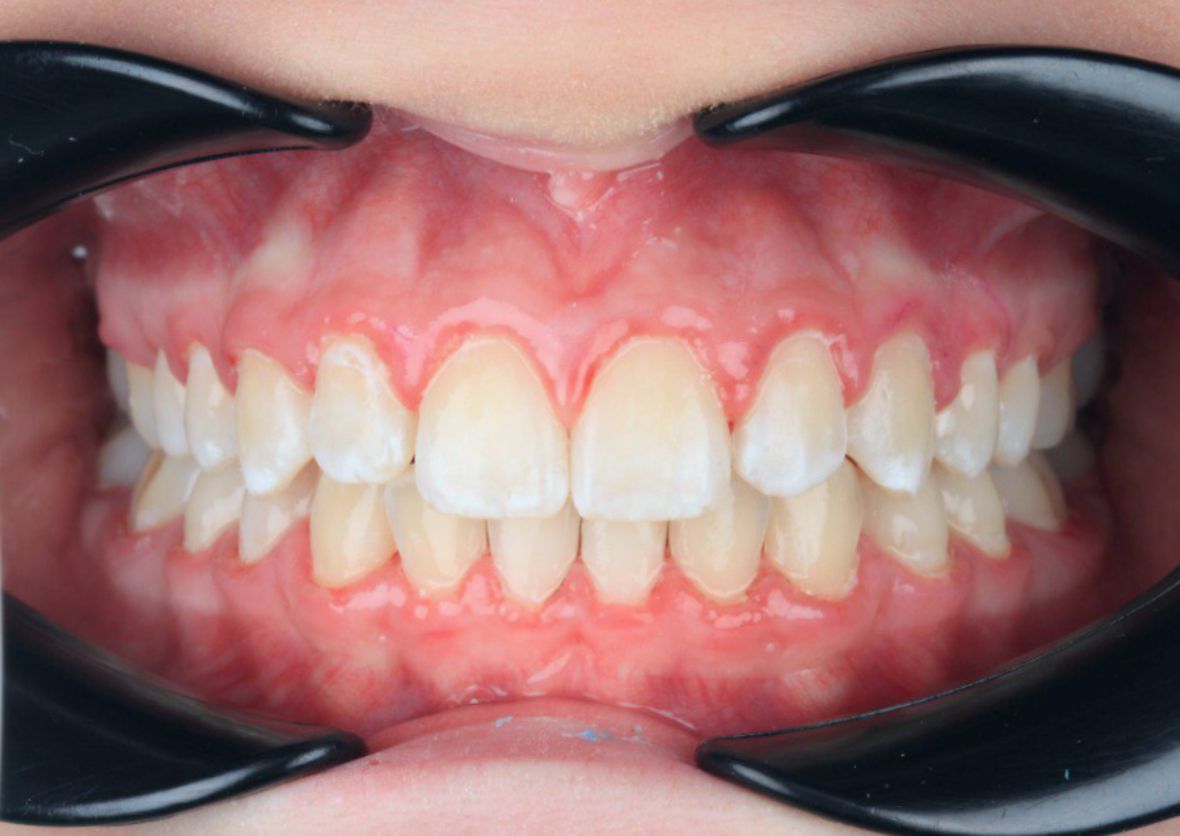

У меня никогда не смыкались зубы полностью и бепокоили клыки. Решила обратиться за консультацией к ортодонту. В завершении лечения понимаю, что это было самым моим лучшим решением-начать лечение на брекет-системе!

Хотела всегда смеяться и не стесняться. Исправлением прикуса в клинике ОК очень довольна! Моя улыбка настолько красива теперь, что я на седьмом небе от счастья

Я всегда мечтала о широкой улыбке, мне не нравился мой наклон зубов. Клиника ОК подарила мне осуществление моей мечты!!